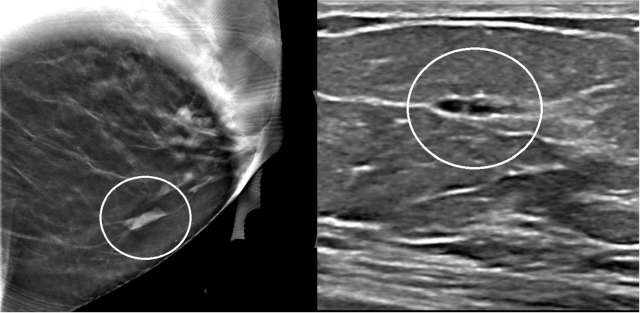

The mammographic appearance of ADH is usually that of grouped or regional calcifications, most often of the amorphous or coarse heterogeneous subtype. ADH can also be less commonly present as a mass or focal asymmetry on screening mammograms. As calcifications are the most common presentation of ADH on screening mammograms, and as ultrasound suboptimally evaluates areas of calcification, ADH is less often seen on ultrasound examinations. However, the most common sonographic feature of lesions demonstrating ADH on ultrasound-guided biopsies includes a hypoechoic, microlobulated mass without acoustic transmission or shadowing. The most common appearance of ADH on breast MRI is nonmass enhancement in a focal, linear, segmental, or regional distribution. The second-most common appearance is that of an enhancing mass.